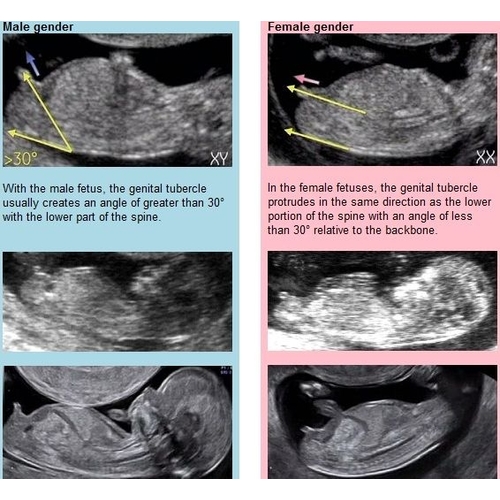

Afgaand op de NUB theorie is mijne een meisje denk ik?